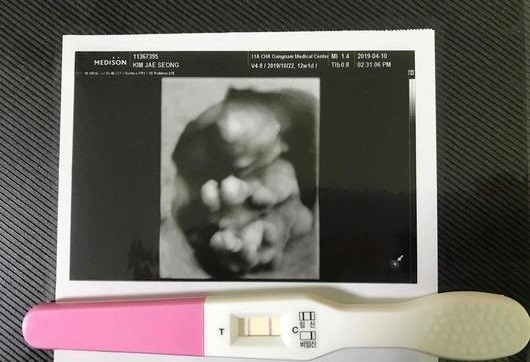

김희원은 16일 자신의 인스타그램에 "2019년 우리에게 온 선물 13주차"라 문구와 함께 한 장의 사진을 업로드했다. 사진 속엔 임신 테스트기와 초음파 사진이 있다.

그는 "임신 초기의 입덧과 몸이 크고 작은 변화들이 어색하고 힘든 순간이지만, 이 모든 것이 지나갈 것이야"라며 "아닌가? 더 큰 변화들이 물밀듯이 밀려오는 거 아니야? 갑자기 무섭네. 모든 엄마들은 대단하십니다! 파이팅!"이라며 심경을 밝혔다.